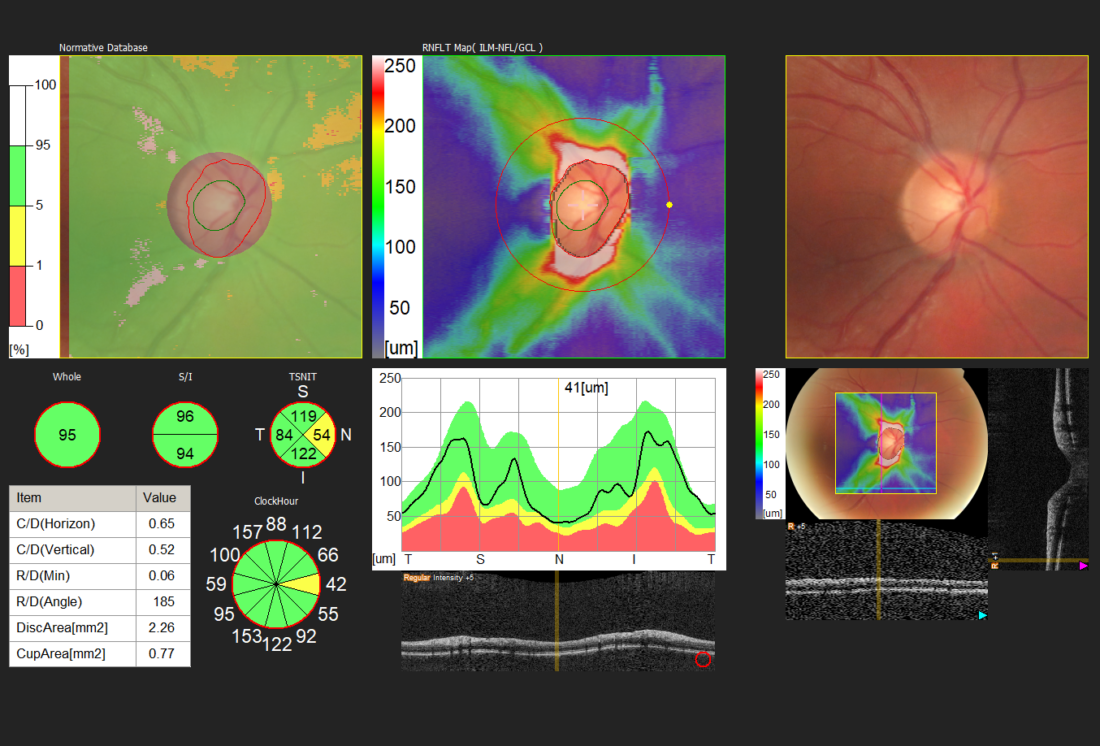

Der Augendruck alleine sagt nicht viel aus. Er muss im Zusammenhang mit der Gesamtsituation des Auges beurteilt werden, insbesondere mit der Erscheinung des Sehnerven (Netzhaut) und der Anatomie der vorderen Augenkammer.

Die Augen Vorsorge Untersuchung heisst bei uns „Panorama Check“, weil unter anderem mit einer Ultra-Weitwinkel Kamera die Netzhaut abgebildet wird. Dazu wird das Auge sorgfältig von vorne bis hinten angeschaut. Besonderer Fokus wird gelegt auf die Netzhaut mit dem Sehnerv und der Makula, aber auch die Augenlinse, die Vorderkammer, die für die Regulierung des Augendruckes wichtig ist. In der heutigen Zeit mit intensiver Bildschirmnutzung wird aber auch der Tränenfilm, die Schleimhaut und die Hornhaut kurz angeschaut. Zudem erfolgen Funktionsteste, um gröbere Auffälligkeiten in der Augenbeweglichkeit oder Pupillenreaktion festzustellen.

Der Augendruck selbst wurde früher als sehr wichtig angeschaut. Er dient zwar auch heute noch als Faktor in der Erkennung, Diagnose und Behandlung eines Glaukoms (eines grünen Stars). Das Verständnis der Krankheit Glaukom hat sich aber grundlegend geändert, da viele Betroffene ein sogenanntes Normaldruckglaukom haben, während andere resilient sind und trotz zu hohem Druck nie einen degenerativen Schaden entwickeln.

Der Augendruck ist also nur eines der Puzzleteile. Nachfolgend sehen Sie Aufnahmen wie sie bei uns im Rahmen eines „Panorama Check“ entstehen.